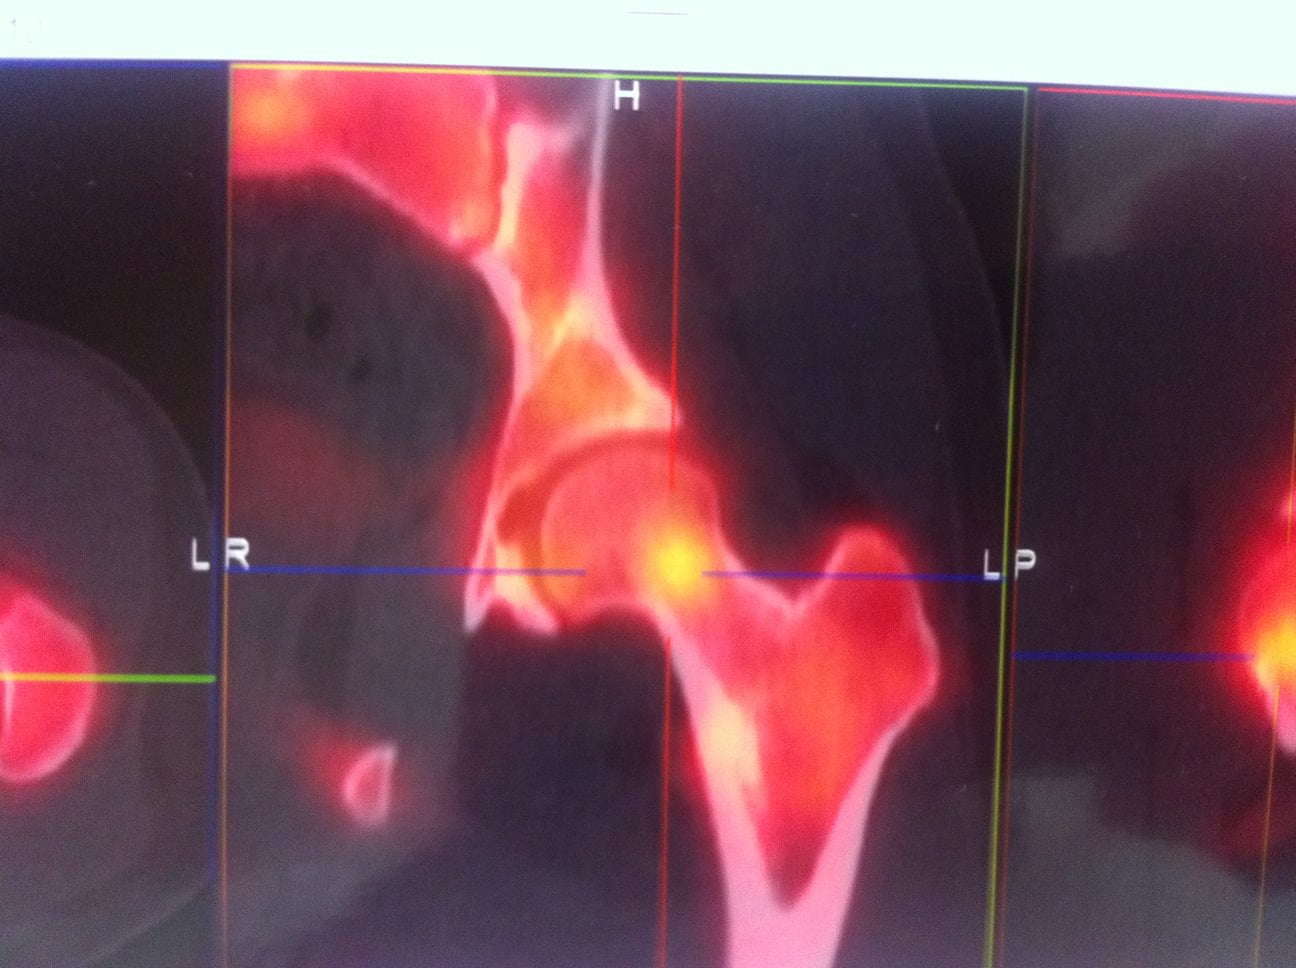

L’Identification est souvent difficile avec un délais diagnostic long. Le diagnostic en imagerie peut aussi porter à confusion dans certains cas. Le plus souvent un scanner avec coupes millimétriques sur l’os atteint suffit à établir le diagnostic. L’IRM et la scintigraphie peuvent apporter une confirmation formelle de la lésion.

Le Nidus = hypodensité à contours nets associé à une hyperdensité calcique linéaire centro-tumorale correspondant à la vascularisation centrale. Une zone hypodense osseuse linéaire au niveau perilésionnel en regard de la condensation est assez spécifique. L’Ostéocondensation périphérique est homogène et peut provoquer une réaction périoste.